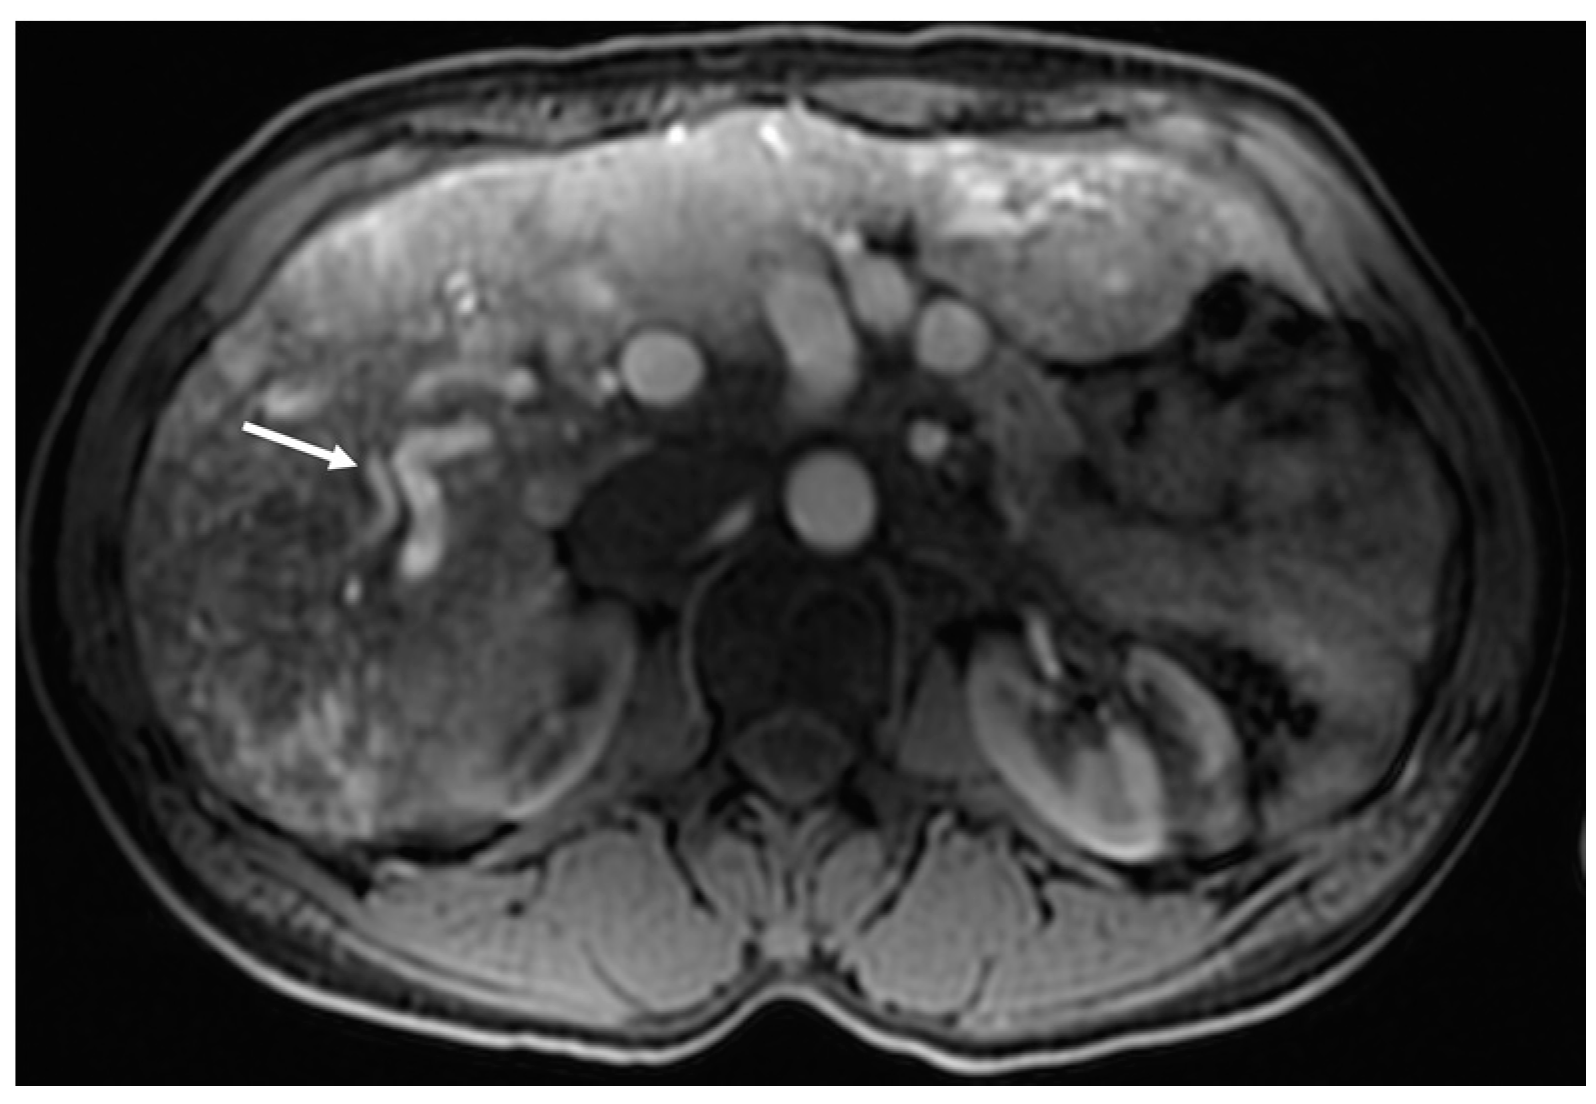

3.2. Arterioportal Shunt